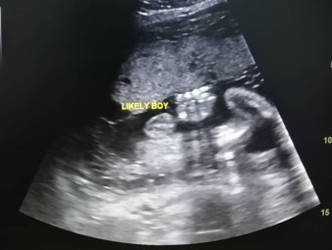

hi moms rasanya ni betul2 boy ke. doc ckap MACAM boy tp knapa sy tgk macam gegurl yang punya

Mana peha dia ek? Confuse pulak tgok. Biasa kalu Dr kata boy. Probably boy.